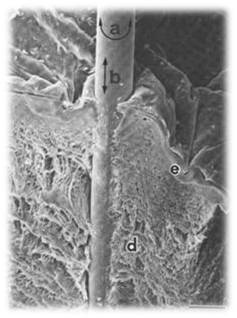

La sensación de llegada de la energía, se refiere fundamentalmente a la sensación que experimentamos los que realizamos la técnica, pero también a la que experimentan los receptores de ella. Una de las preguntas más formuladas sobre la técnica de la acupuntura es si debe sentirse especialmente o no la experiencia de ser punturado.

En nuestra práctica clínica nos encontramos con que algo de lo más real esta ocurriendo. Los pacientes se expresan y coinciden, dentro de la particularidad de su identidad. El paciente experimenta sensaciones características de la llegada o no de la energía. Cuando la energía llega el paciente habla de:

- Hinchazón

- Entumecimiento

- Calor

- Quemor

- Impresión de difusión y de conducción

- El punto

- Irradiando

- En capa

- Linear (PSC)

Por otro lado, podemos hablar de nuestra propia experiencia como practicantes y comprobar que nuestras sensaciones coinciden con la de otros compañeros, y tal vez, esto pueda servirnos para dar luz y favorecer una actitud humilde al percatarnos que es más lo que nos une que lo que nos separa. El terapeuta expresa sensaciones como: » una resistencia» » como si algo apretara desde dentro» «sensación de agarre» (Grasp Needle)